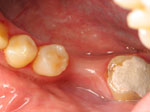

Permanent bridges will do just that! Brush them, floss them and take care of them just like your natural teeth…. and get ready for that steak dinner!!